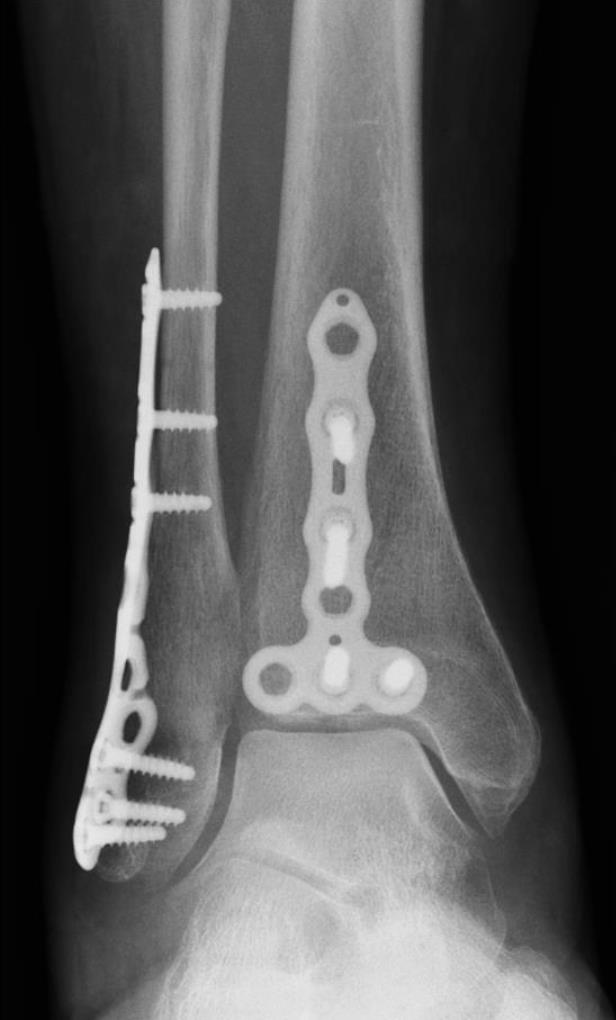

Volition® Ankle Fracture Plating

• VolitionTM Ankle Fracture Plates are available in six varieties: anatomic fibula plate, straight fibula plate, anatomic medial malleolar plate, posteromedial tibial plates (Type IIB), posterolateral tibial plates (Type IIA) and posterior tibial plates (Type III).

• lateral anatomical fibular plate

• posterolateral tibial plates (type iia)

• posteromedial tibial plates (type iib)

• posterior tibial plates (type iii)

• medial plate

• straight plate